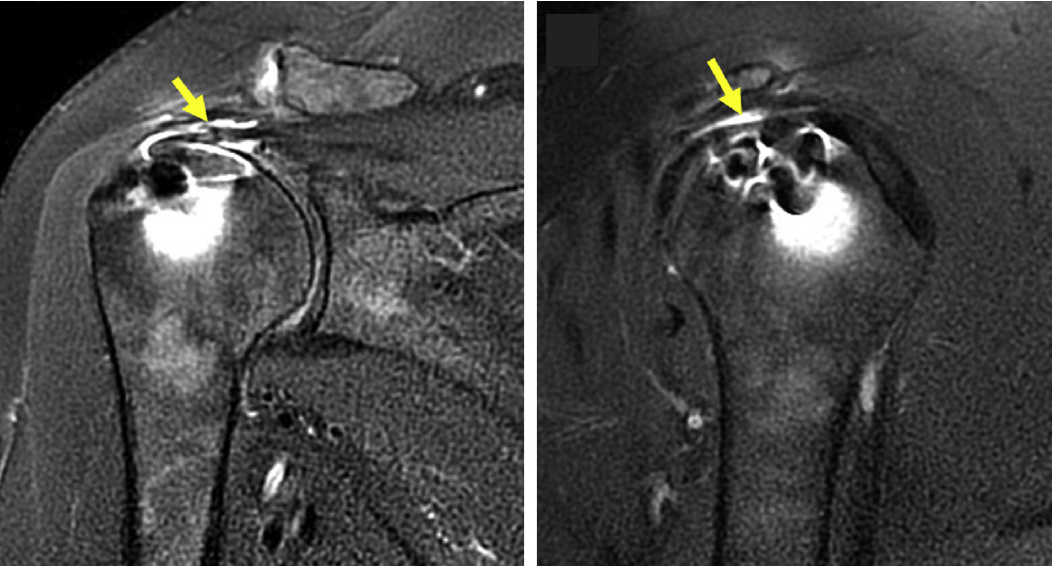

È stato dimostrato che la DEGENERAZIONE IN GRASSO del ventre muscolare è un cambiamento irreversibile correlato ad una maggiore incidenza di fallimento della riparazione della cuffia dei rotatori.

Confrontando tra loro le diverse tecniche chirurgiche esistenti per riparare la cuffia dei rotatori, i risultati sono contrastanti. Tecniche più complesse di riparazione della cuffia dei rotatori, quali tecnica “double row” o “transosseous equivalent”possono sicuramente diminuire il rischio di recidiva nelle lesioni di più ampie dimensioni. Tuttavia queste tecniche più complesse sono associate ad una ROTTURA DELLA GIUNZIONE MIOTENDINEA che sono tra le forme più gravi di recidiva della lesione delle cuffia rotatori.

Una recidiva di lesione della cuffia rotatori può essere classificata alla RMN come Tipo 1 (assenza di tendine residuo a livello dell’inserzione su trochite) o Tipo 2 (il tessuto residuo della cuffia è rimasto nel sito di inserzione) Il fallimento di Tipo 1 può essere correlato sia a un fallimento meccanico che a un fallimento della guarigione biologica, mentre il fallimento di Tipo 2 implica una nuova rottura di una riparazione guarita.